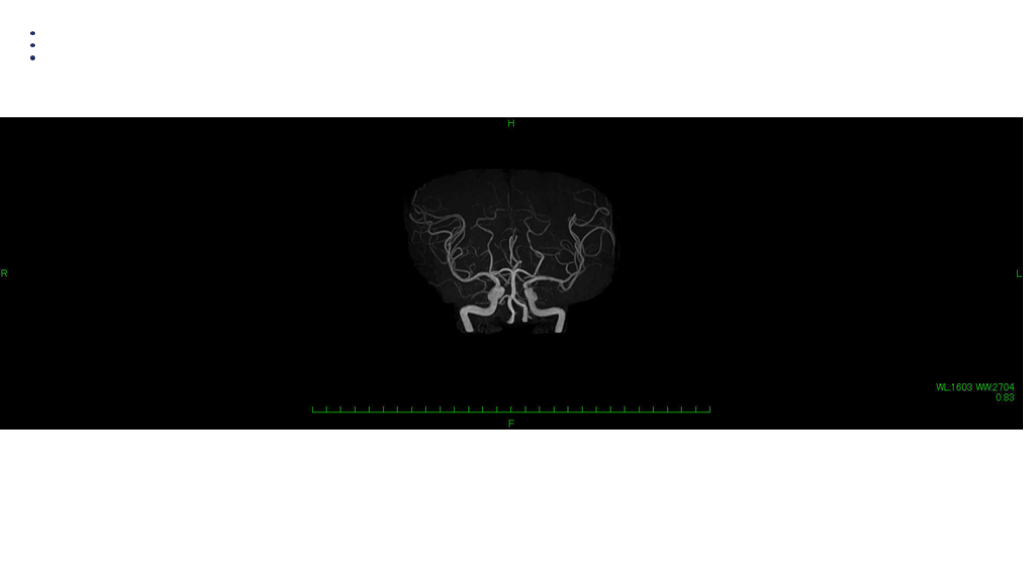

画像 所見 DAY 30 MRA 改善